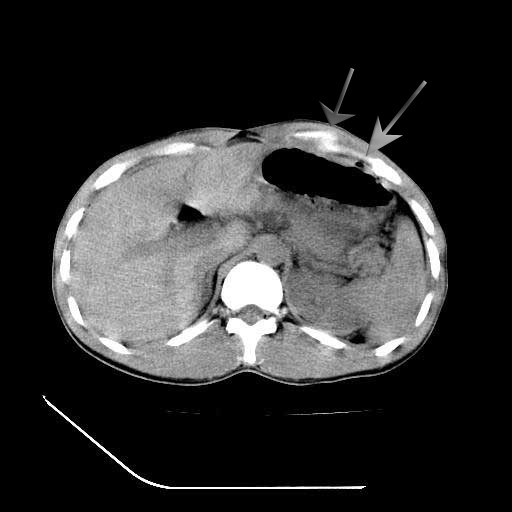

顺便请各位老师认真看看7号片

各位老师觉得胆囊是不是有点积血。我在原始片看胆囊密度不均,似有小液平面

再有就是支持楼主,胆囊7日片比5日片不仅增大许多,靠后下更见液液分层,应该是有积血。